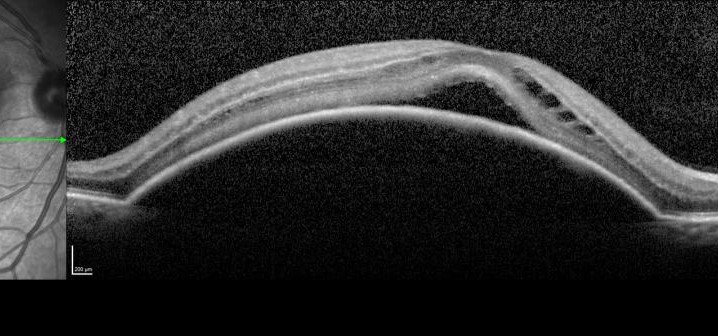

Inyecciones intravítreasDMAE seca o atróficaDMAE exudativa o húmedaRetinografíaAutofluorescenciaAngiografía fluoresceínicaAngiografía con verde de indocianinaTomografía de coherencia ópticaAutor